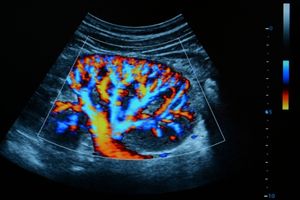

سونوگرافی قلب (اکوکاردیوگرافی): این نوع سونوگرافی برای بررسی وضعیت قلب و رگهای خونی استفاده میشود. اکوکاردیوگرافی به پزشکان کمک میکند تا مشکلات قلبی مانند نقصهای دریچهای، ضعف قلب و اختلالات جریان خون را شناسایی کنند.